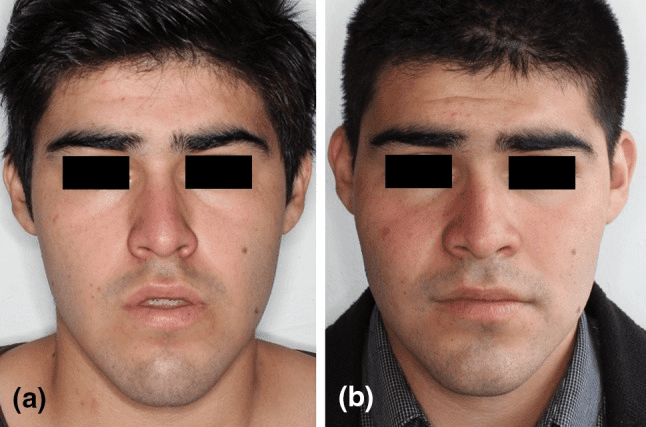

It moves cheekbones upward, give so much under eye support and even change orbital shape. Also widen face and change gonial angle. Is it modified lefort 3?